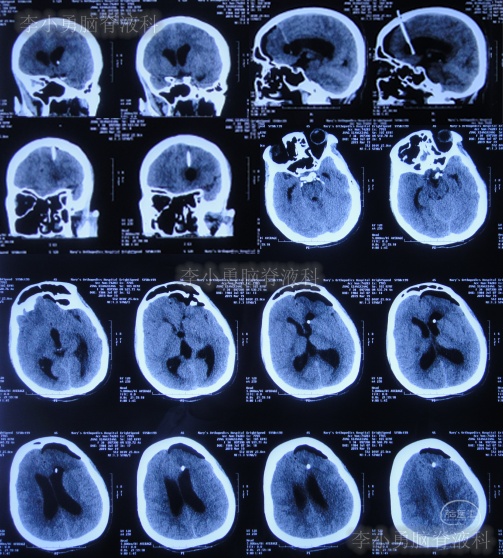

入院治疗9天即2019年3月28日,体温变正常,进行了右侧侧脑室腹部外引流术。

入院治疗42天即2019年5月9日,头痛和体温均已完全正常近1月,查颈椎核磁示脊髓空洞有变小(图-16)。

入院治疗48天即2019年5月15日,进行了右侧脑室-腹腔分流术(图-17)。

图-17:2019年5月15日头颅CT

入院治疗58天即2019年5月25日,康复出院。出院时:神清气爽,身体完全正常(图-18)。